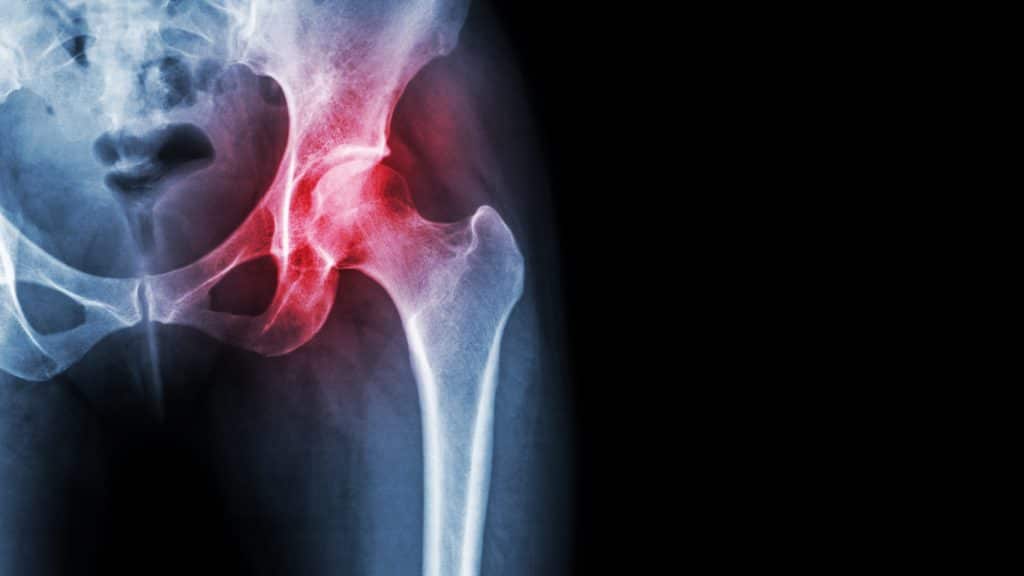

Osteoartróza kyčelního kloubu

Nejčastěji se vyskytuje u dospělých ve věku nad 40 let. Mezi příznaky patří bolest, postižení, ambulantní dysfunkce a ztuhlost/kontrakce. Pacient obvykle pociťuje bolest v přední části třísla a příležitostně v hýždi a boční části stehna. U některých pacientů se může objevit generalizovaná bolest kyčle přenášená do kolene. Je velmi důležité zvážit a/nebo vyloučit koexistující patologii/radikulopatii kyčle a ipsilaterální onemocnění kolene.

Patogeneze zahrnuje opotřebení kloubní chrupavky, které časem vede ke zmenšení ochranného kloubního prostoru. Kosti se o sebe začnou třít a snaží se nahradit ztracenou chrupavku, čímž vznikají kostní ostruhy nebo osteofyty. Nechirurgická léčba zahrnuje změnu životního stylu, například snížení hmotnosti nebo minimalizaci činností, které bolest zhoršují. Jako účinné se ukázaly také fyzikální terapie, používání asistenčních pomůcek a léků, jako jsou NSAID, paracetamol a kortikosteroidy. U pacientů, jejichž bolest je stále nezjistitelná, může být nutný chirurgický zákrok. Mezi chirurgické možnosti patří osteotomie, resurfacing kyčelního kloubu a totální náhrada kyčelního kloubu